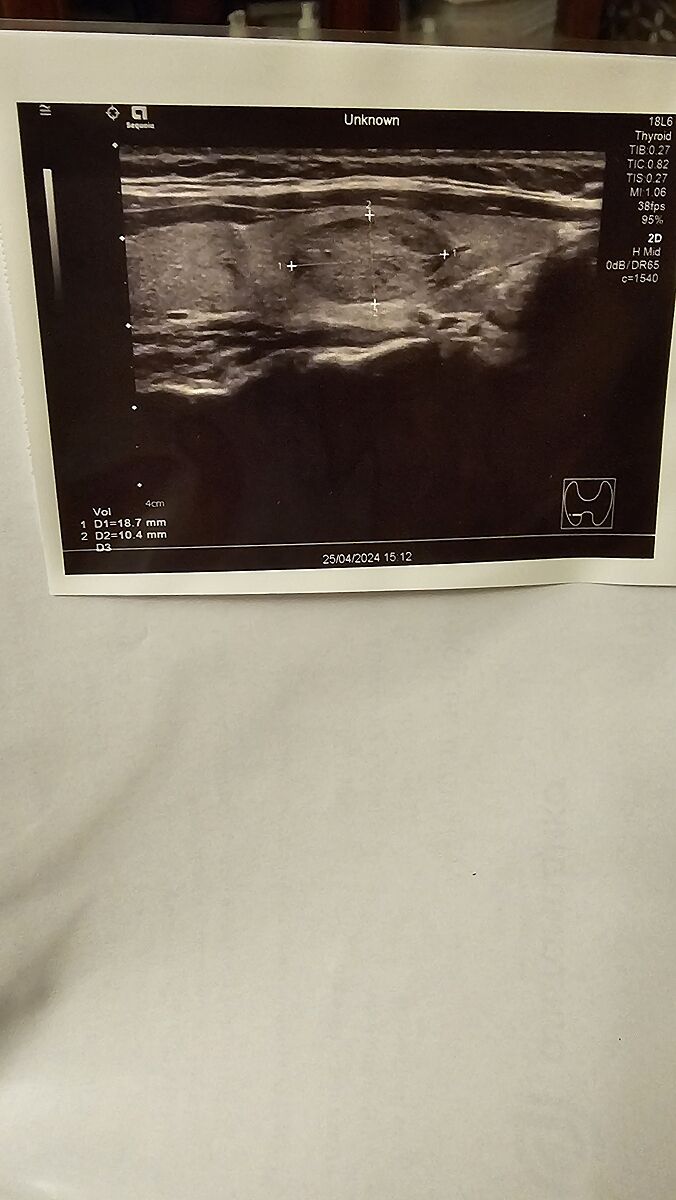

Нашелся на узи узел,что с ним делать,и что это?

Так без описания смысл в фото? Тирадис узла?

Там есть на фотке размер сбоку

Какой тирадс? 1,2,3- наблюдать

Локация написано на фото и размеры тоже

Мелкий,18×10×15 мм

Це великий. Маленький це до 10 мм.

А опис УЗІ? Там все розписано повинно бути, розмір, края, ехогенність і т.д,

Це не малий вузол. Більше 1см - біопсія потрібна.

Это все ни о чем. Автор упорно молчит об описании узла, есть ли включения, капсула, кровоток. По виду не супер страшно, ну и повторюсь тирадис какой?

Анехогені включення то не дуже добре, мабуть буде біопсія.

фото